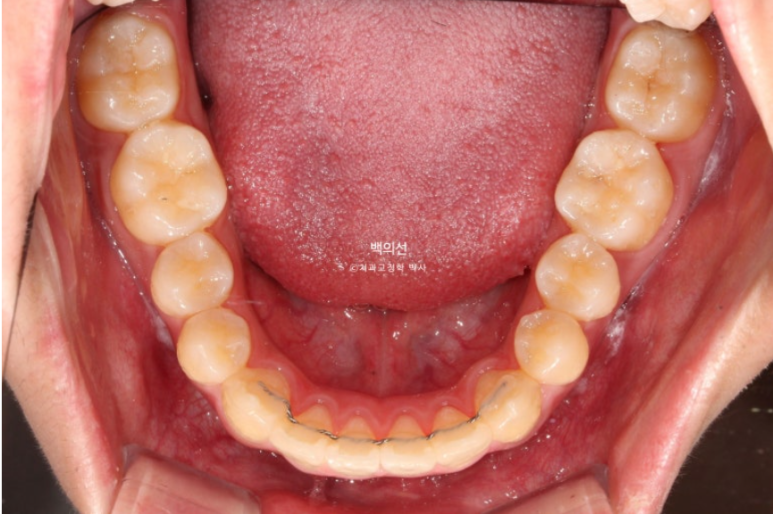

24.12

배열도 완벽 합니다.